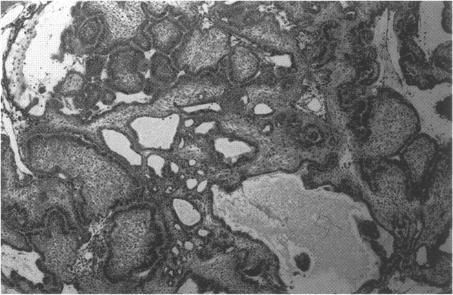

Although craniopharyngiomas account for a large percentage of pediatric intracranial tumors, there is a bimodal age distribution. Most of these neoplasms are suprasellar or sellar in location. In this report we describe an unusual case of an infrasellar craniopharyngioma in a child. Only four previous cases of infrasellar craniopharyngiomas with no sellar involvement have been described. Infrasellar craniopharyngiomas are part of the continuum representing intracranial craniopharyngiomas and ameloblastomas of the jaw. A transnasal endoscopic biopsy was performed with a preliminary diagnosis of craniopharyngioma. The patient then underwent a radical resection of the infrasellar tumor via a subfrontal transbasal approach. This case illustrates a rare and unusual location for a craniopharyngioma. Craniopharyngiomas should be considered in the differential diagnosis of infrasellar neoplasms. Infrasellar craniopharyngiomas compromise part of the spectrum of tumors originating from enamel-forming neural crest cells.

尽管颅咽管瘤在儿童颅内肿瘤中占很大比例,但存在双峰年龄分布。这些肿瘤大多位于鞍上或鞍区。在本报告中,我们描述了一例儿童鞍下颅咽管瘤的罕见病例。此前仅报道过4例无鞍区受累的鞍下颅咽管瘤病例。鞍下颅咽管瘤是颅内颅咽管瘤和颌骨成釉细胞瘤连续谱系的一部分。进行了经鼻内镜活检,初步诊断为颅咽管瘤。然后患者通过额下经基底入路对鞍下肿瘤进行了根治性切除。该病例说明了颅咽管瘤的一个罕见且不寻常的位置。在鞍下肿瘤的鉴别诊断中应考虑颅咽管瘤。鞍下颅咽管瘤是起源于形成釉质的神经嵴细胞的肿瘤谱系的一部分。